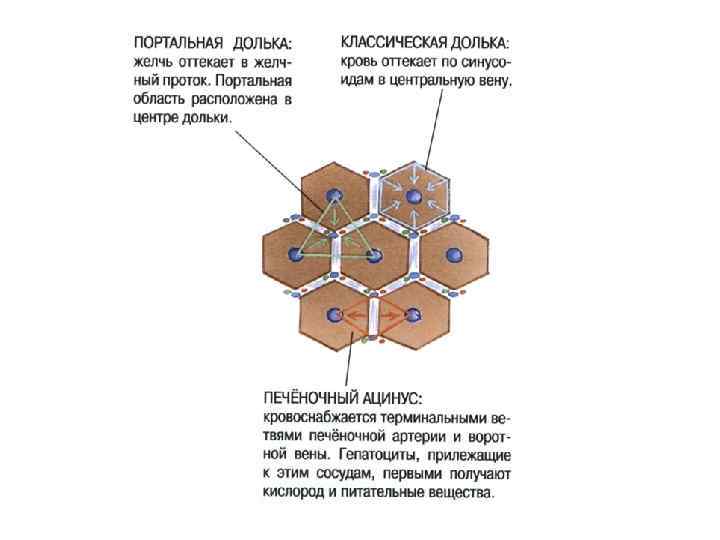

1 - зона оптимального кровоснабжения, 2 - зона умеренного кровоснабжения, 3 - зона наихудшего кровоснабжения (наиболее уязвима при интоксикациях)